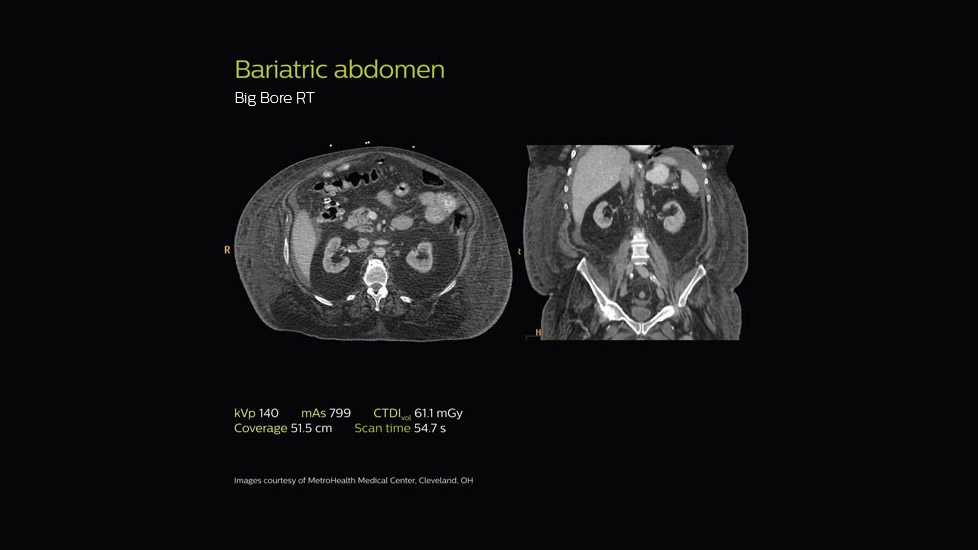

Клинические изображения

Специализированный КТ-сканер Philips CT Big Bore для онкологии, КТ-симуляции и радиационного планирования. Он соответствует стандартам MITA XR-25 и XR-29, обеспечивая интеллектуальный контроль дозы и отвечает международным требованиям лучевой безопасности. Нагрузка стола: до 295 кг.

Абдоминальная и тазовая локализация

- Визуализация мягкотканных опухолей (печень, почка, поджелудочная железа, органы таза) с контурированием OAR,

- Возможность КТ-анализов с контрастированием в артериальную, венозную и позднюю фазы,

- Использование для расчета смещения мочевого пузыря и прямой кишки в динамике.